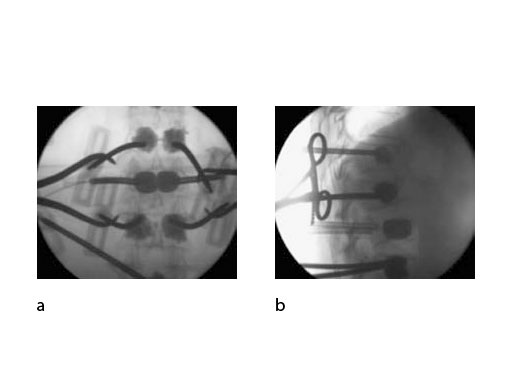

Both guide wire and trocar can be inserted through either a transpedicular (Fig 2a) or extrapedicular (Fig 2b) approach. The trocar allows access in a single step while the wire guide is first used to create a path for the access instruments.